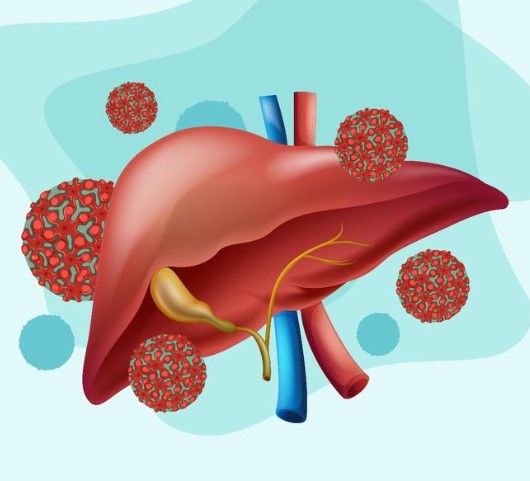

المضاعفات المحتملة لالتهاب الكبد الفيروسي

رغم أن كثيرًا من حالات التهاب الكبد الفيروسي يمكن التعافي منها، إلا أن إهمال العلاج أو تطور العدوى في بعض الأنواع قد يؤدي إلى مضاعفات صحية خطيرة تمس وظائف الكبد وصحة الجسم بشكل عام. أبرز هذه المضاعفات:

ضعف الجهاز المناعي: يمكن أن يؤثر الفيروس على كفاءة الجهاز المناعي، مما يجعل الجسم أكثر عرضة للعدوى الأخرى.

تلف أنسجة الكبد: قد يؤدي استمرار الالتهاب إلى تدمير تدريجي لخلايا الكبد، مما يؤثر على كفاءته الحيوية.

فشل وظائف الكبد: في الحالات المتقدمة، قد يفقد الكبد قدرته على أداء وظائفه الأساسية بشكل طبيعي.

سرطان الكبد: الالتهابات المزمنة طويلة الأمد قد تزيد من احتمالية تطور أورام خبيثة في الكبد.

سهولة انتقال العدوى: بعض أنواع الفيروسات تتميز بقدرتها العالية على الانتشار من شخص لآخر، مما يزيد من خطورة تفشي المرض.

الوفاة في حالات نادرة: عند غياب التدخل الطبي أو في الحالات الشديدة جدًا، قد تصل المضاعفات إلى نتائج خطيرة تهدد الحياة.